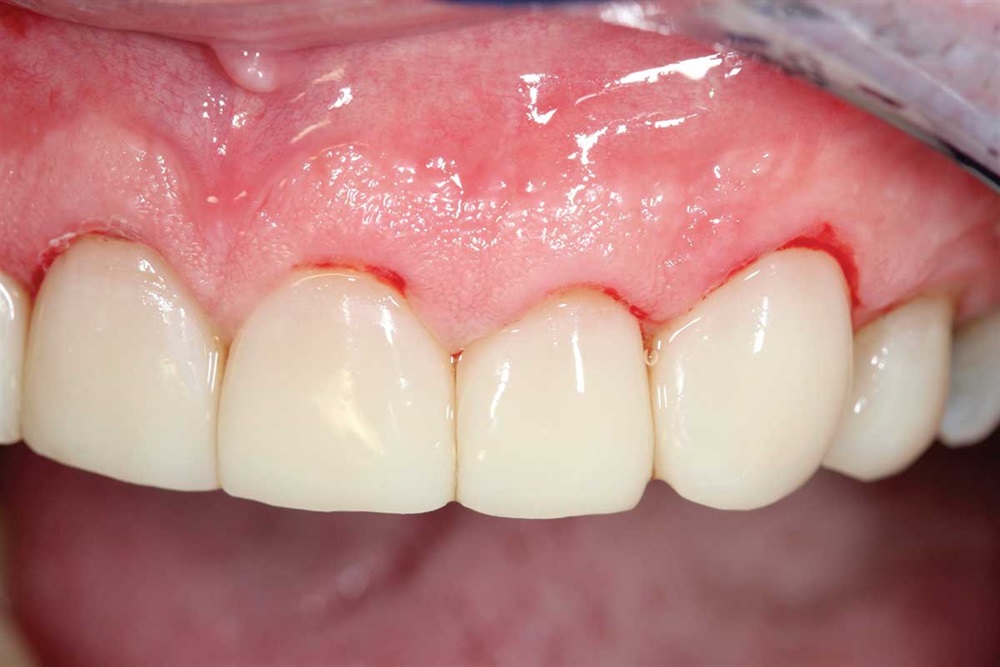

Show Your Work

Fig. 43: Finished. If you have not tried Renamel, you really owe it to yourself and your patients to get a syringe and see how nice it looks. Dr. Buddy Mopper brought it to market well over 25 years ago.